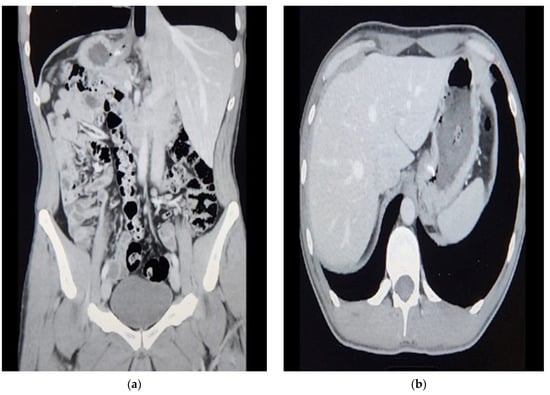

Barium swallow showed a dilatation of the esophagus with evidence of breaking at the gastroesophageal junction. There were no filling defects or masses in the esophagus. The contrast passes slowly to the stomach, which appears unremarkable. There was no reflux in the delayed images. The mucosa appears smooth, with no thickening or ulceration. There is no evidence of diverticulae, tertiary contrast shoulder, or dysmotility. The impression was that the thickening was describing the fundoplication wrap. Given the anti-inflammatory protocol to reduce edema, we kept him NPO.

On 2 February 2023, the patient felt better and was able to drink fluids with no problems, no dysphagia, no reflux, and no vomiting. During the post-operative observation, he recovered smoothly and tolerated oral intake, and the workup showed stable hemoglobin and a normal white blood count. In addition, a barium swallow demonstrated no filling defect, no reflux, and that the contrast was passing to the stomach nicely. On the second day following the operation, he tolerated oral intake, reported no reflux, and passed gases. Furthermore, he was pain-free and mobilized; as a result, he was ready to go home after fulfilling the discharge criteria. The patient was ready to be discharged home, fit the criteria of discharge, passed gases, and tolerated oral intake.

Figure 1. CT scan of the abdomen pelvis: (a) Coronal; (b) Transverse. Suspicious increased wall thickening of the proximal stomach extending to the gastroesophageal junction.